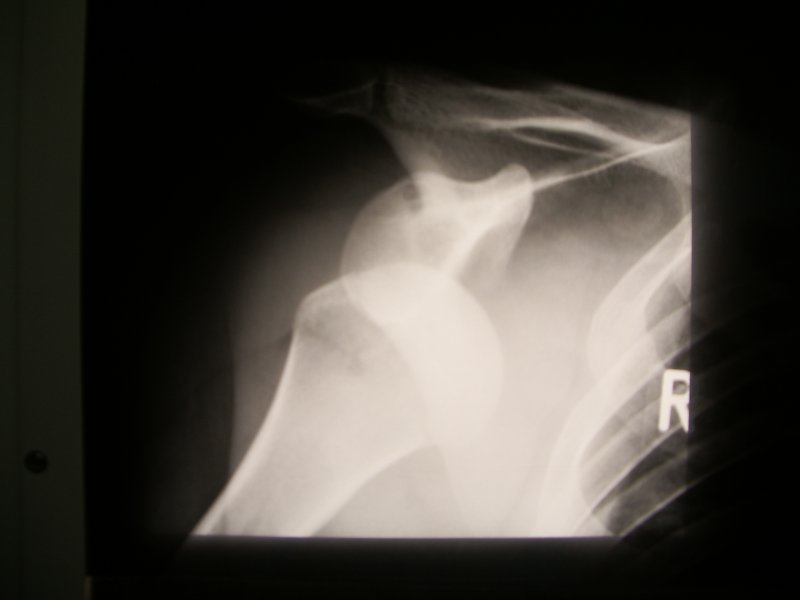

Zwichniecie barku ( Luxatio humerii )

Przy zwichnięciu barku u młodych ludzi, czesto oderwany zostaje obrabek stawowy (labrum glenoidale) od panewki (glenoid). Wygląda to tak jakby opona spadła z felgi koła samochodowego, w medycynie nazywa sie to Bankart Lesion. Ponieważ brak obrąbka stawowego na panewce powoduje po pierwszym zwichnieciu prawie zawsze niestabilność i następne zwichnięcia, powinno się zrekonstruować anatomiczna pozycje (czyli naciagnac oponę na felgę) obrąbka stawowego.